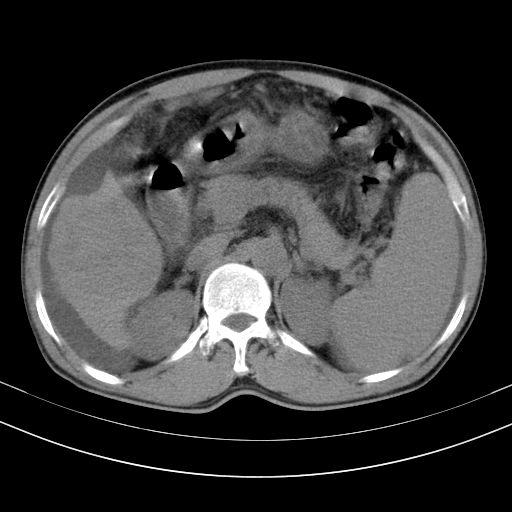

以下是引用随光逐影在2010-2-28 10:23:00的发言:[br]1)考虑肝癌;建议行ct增强扫描检查。2)肝硬化,脾大,腹水。3)慢性胆囊炎。

以下是引用dyqct在2010-2-28 16:44:00的发言:[br][quote]以下是引用随光逐影在2010-2-28 10:23:00的发言:[br]1)考虑肝癌;建议行ct增强扫描检查。2)肝硬化,脾大,腹水。3)慢性胆囊炎。